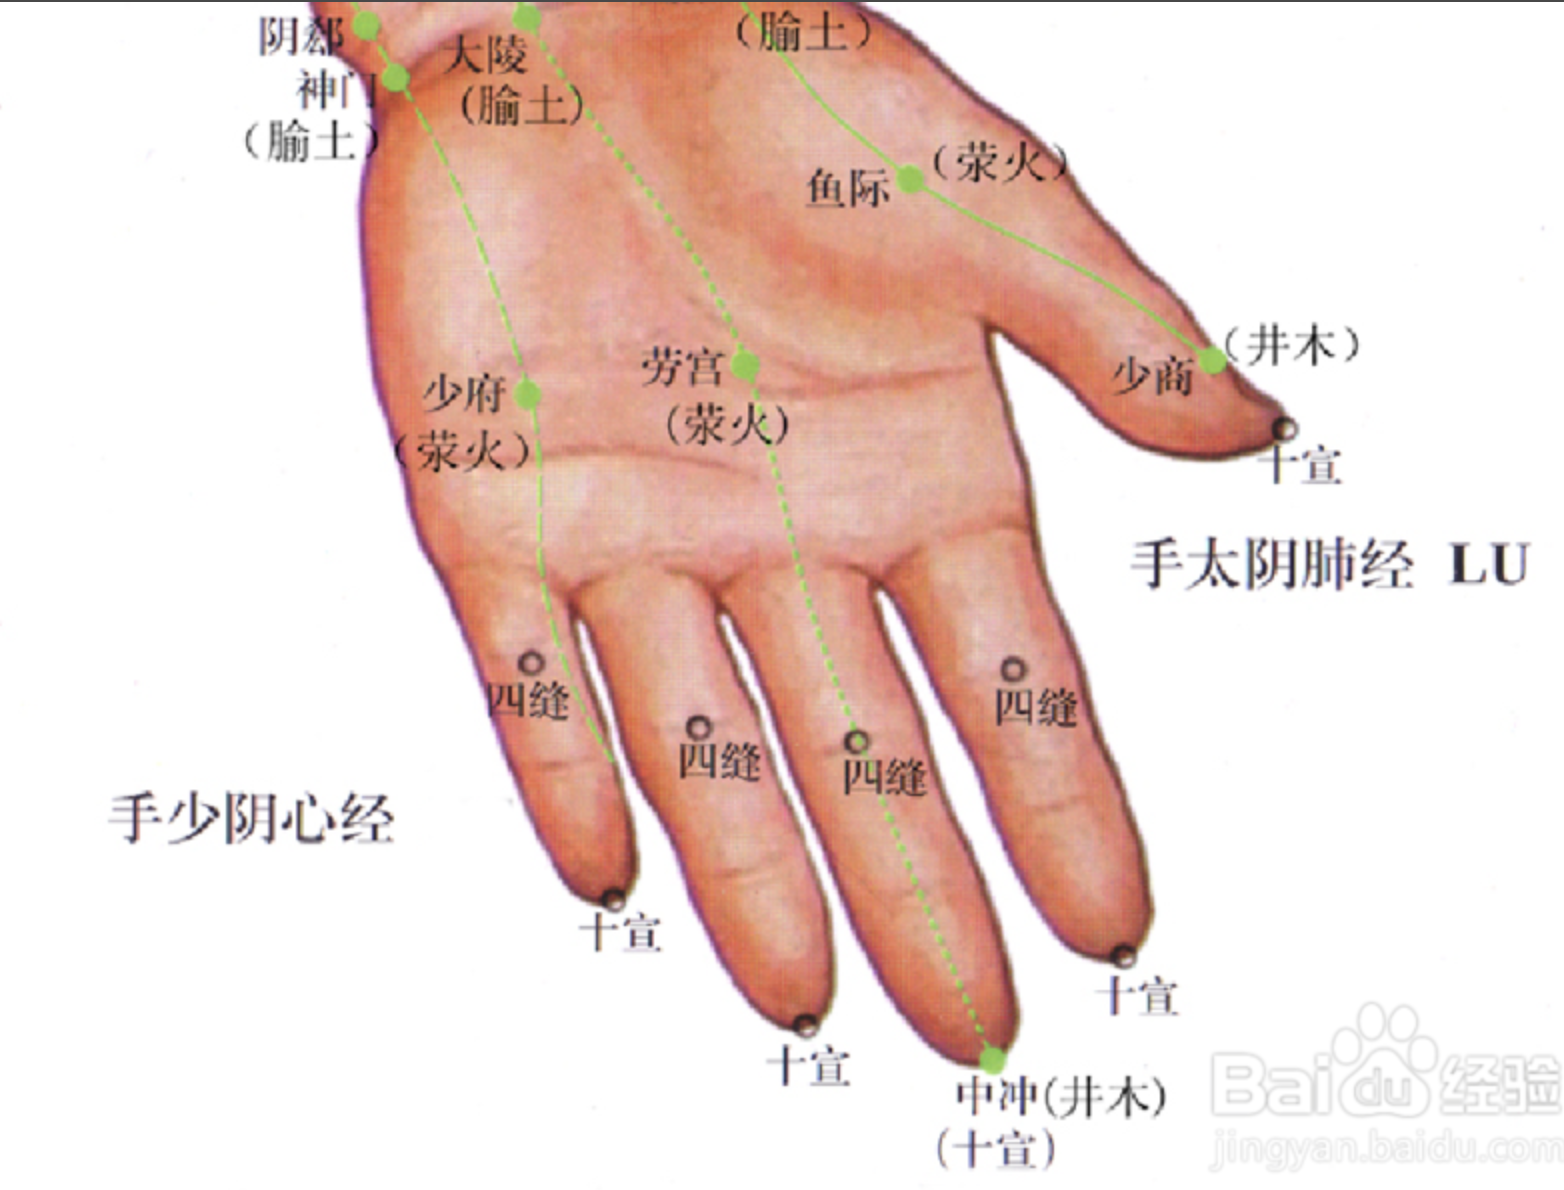

四缝

【定位】 在第 2 至第 5 指掌侧,近端指关节的中央,一手 4 穴,左右共 8 穴(图 10-36)。

【主治】 小儿疳积,百日咳。

【刺灸法】 点刺出血或挤出少许黄色透明黏液。

十宣

【定位】 在手十指尖端,距指甲游离缘 0.1 寸(指寸),左右共 10 穴(图10-36)。

【主治】 昏迷,癫痫,高热、咽喉肿痛。

【刺灸法】 浅刺 0.1 ~ 0.2 寸,或点刺出血。